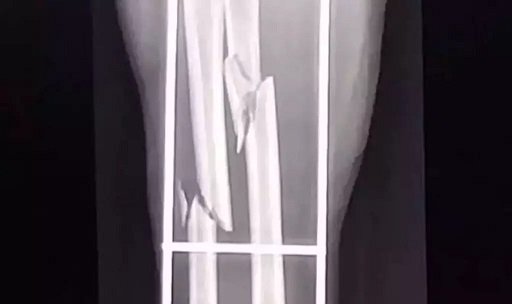

Radiografia mostra a fratura no braço da mulher (Foto: divulgação / Polícia Civil)

Conforme a Polícia Civil, a vítima e o marido estavam em casa, quando foram surpreendidos pelo suspeito e agredidos a pauladas. A mulher sofreu fratura no antebraço e o seu companheiro teve três costelas quebradas.